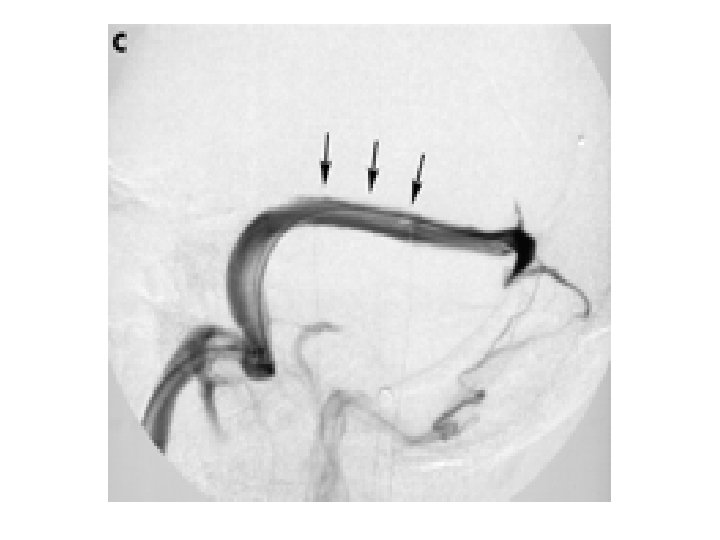

Sinus Stenosis: Blockage or compression? Normal Stenosed Sinus J N P Higgins, C Cousins, B K Owler, N Sarkies and J D Pickard Idiopathic intracranial hypertension: 12 cases treated by venous sinus stenting Journal of Neurology Neurosurgery and Psychiatry 2003; 74: 1662 -1666